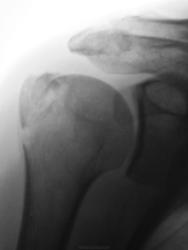

Виновата жена..., упал с дерева...

Данный перелом чреват развитием импиджмент-синдрома

импиджмент-синдром чреват нарушением функции плечевого сустава

нарушение функции плечевого сустава чревато невозможностью более лазить по деревьям